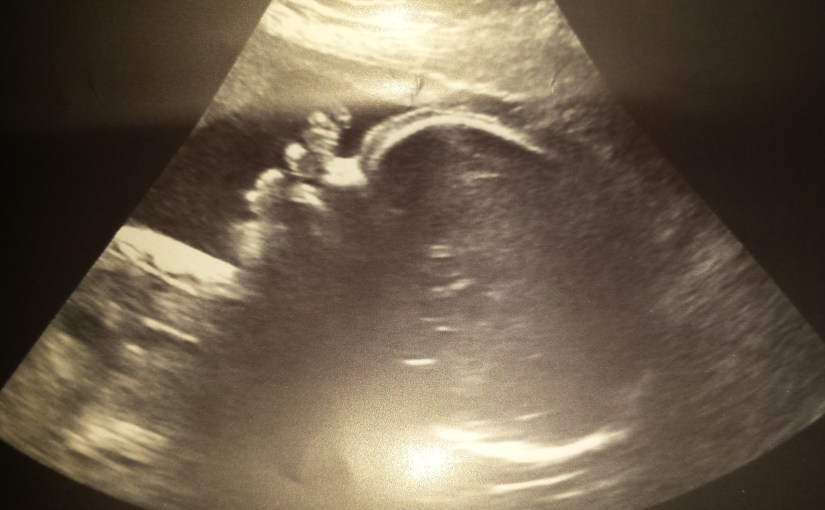

After school Madison headed to Nana’s for the afternoon. After lunch she played with her new Christmas puzzle, her baby and practiced finding her letters on the keyboard. When Mommy and Daddy picked her up after their appointment, Madison saw new pictures of her baby brother. Madison was very excited to show Nana and Mommy and Daddy were happy to report that baby #2 is doing great and is 30 weeks today!